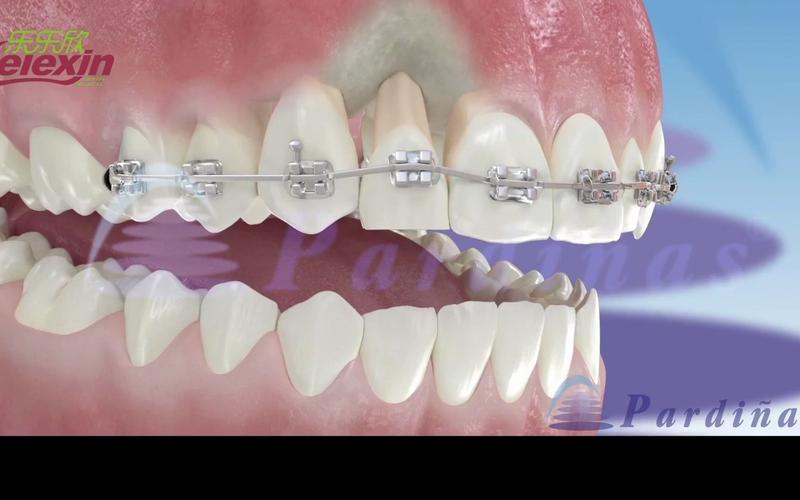

正畸牵引圈是正畸治疗中常用的辅助装置,主要用于牵引牙齿、关闭间隙、纠正牙齿位置异常等,其弯制质量直接影响治疗效果和患者舒适度,弯制正畸牵引圈需要结合牙齿解剖形态、移动方向及生物力学原理,通过精细操作实现精准形态,以下从工具准备、弯制步骤、技巧要点、常见问题及解决方法等方面详细说明正畸牵引圈的弯制方法。

- 弯制圆形主体:保持钢丝与钳口垂直,细丝钳钳尖沿折角方向旋转,同时向内施加压力,弯制半圆弧(约180°);翻转钢丝,对称弯制另一侧半圆,形成完整圆形。

- 调整对称性:用卡尺测量主体直径,若两侧不对称,用梯形钳轻柔调整弧度,确保圆周均匀。

- 调整弧度贴合度:将弯制好的牵引圈放在模型或石膏牙上,检查是否与牙冠表面贴合,避免压迫牙龈乳头;若不贴合,用细丝钳轻柔调整主体弧度,直至牵引圈能稳定套入牙冠且无翘动。

- 修整牵引钩方向:用梯形钳调整牵引钩角度,确保牵引力方向与牙齿移动方向一致(如牵引尖牙远中移动,牵引钩应指向远中偏龈方)。